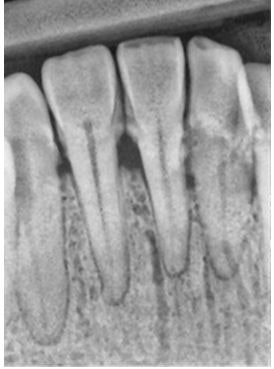

A similar type of evaluation can be done with periodontal disease using XDR software by Cyber Nedical Imaging.

On the left below is the initial radiograph, and on the right is the radiograph after enhancing the image.

![]() ![]() |